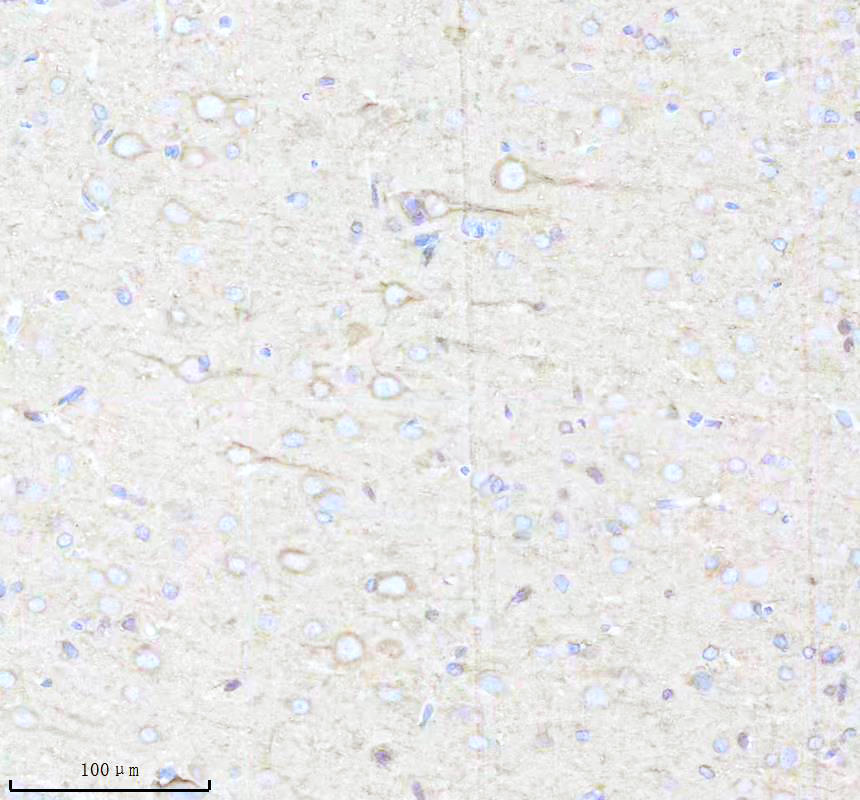

IHC analysis of BNIP3L using anti-BNIP3L antibody (BM5174) .

BNIP3L was detected in a paraffin-embedded section of rat brain tissue. The tissue section was incubated with rabbit anti-BNIP3L Antibody (BM5174) at a dilution of 1:200 and developed using HRP Conjugated Rabbit IgG Super Vision Assay Kit (Catalog # SV0002) with DAB (Catalog # AR1027) as the chromogen.

IHC analysis of BNIP3L using anti-BNIP3L antibody (BM5174) .

BNIP3L was detected in a paraffin-embedded section of rat brain tissue. The tissue section was incubated with rabbit anti-BNIP3L Antibody (BM5174) at a dilution of 1:200 and developed using HRP Conjugated Rabbit IgG Super Vision Assay Kit (Catalog # SV0002) with DAB (Catalog # AR1027) as the chromogen.